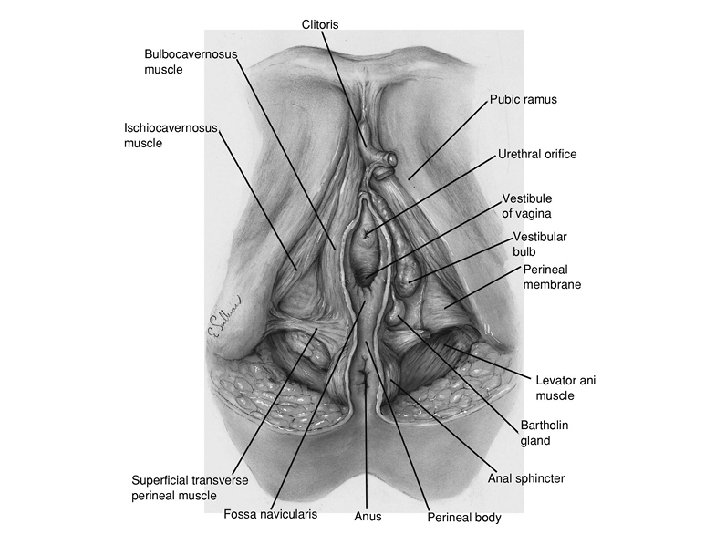

Layers of the Anterior Triangle of the Perineum • Skin • Subcutaneous tissue . Camper's fascia . Colles fascia • Superficial space . Clitoris and its crura . Ischiocavernous muscle . Vestibular bulb . Bulbocavernous muscle . Greater vestibular gland . Superficial transverse perineal muscle • Deep space-perineal membrane . Compressor urethrae . Urethrovaginal sphincter

• Ürogenital trigon: – – M. Transversus perinei superficialis M. İschiocavernosus M. Bulbocavernosus M. Transversus perinei profundus • Anal trigon: – M. Levator ani – M. Sphincter ani externus

FIGURE 7. 2. Superficial compartment and perineal membrane.

FIGURE 7. 2. Superficial compartment and perineal membrane.